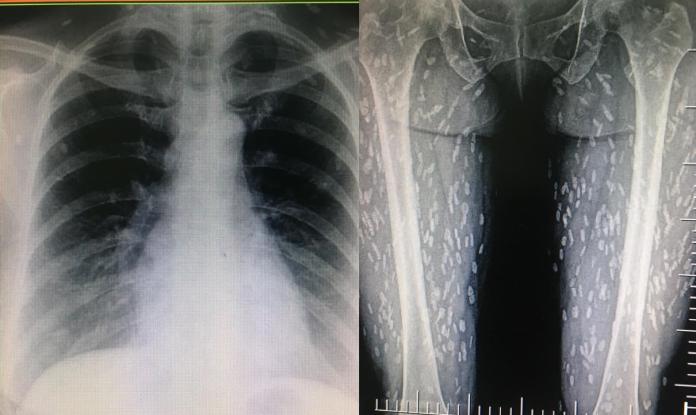

女子生吃豬肉…照X光「上百寄生蟲」在體內

豬肉絕對不能生吃!泰國一名女子因為生吃豬肉,結果身體竟被數百隻絛蟲寄生。該名女子因為出現呼吸困難等症狀前往醫院檢查,一照X光片才發現絛蟲遍佈她的全身,...